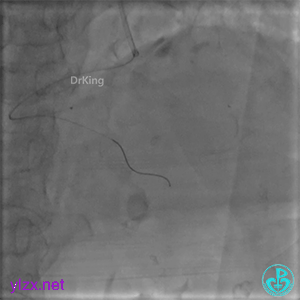

1周后复查冠脉造影

PL主支通畅,远端一个小分支丢失,未见破口存在。